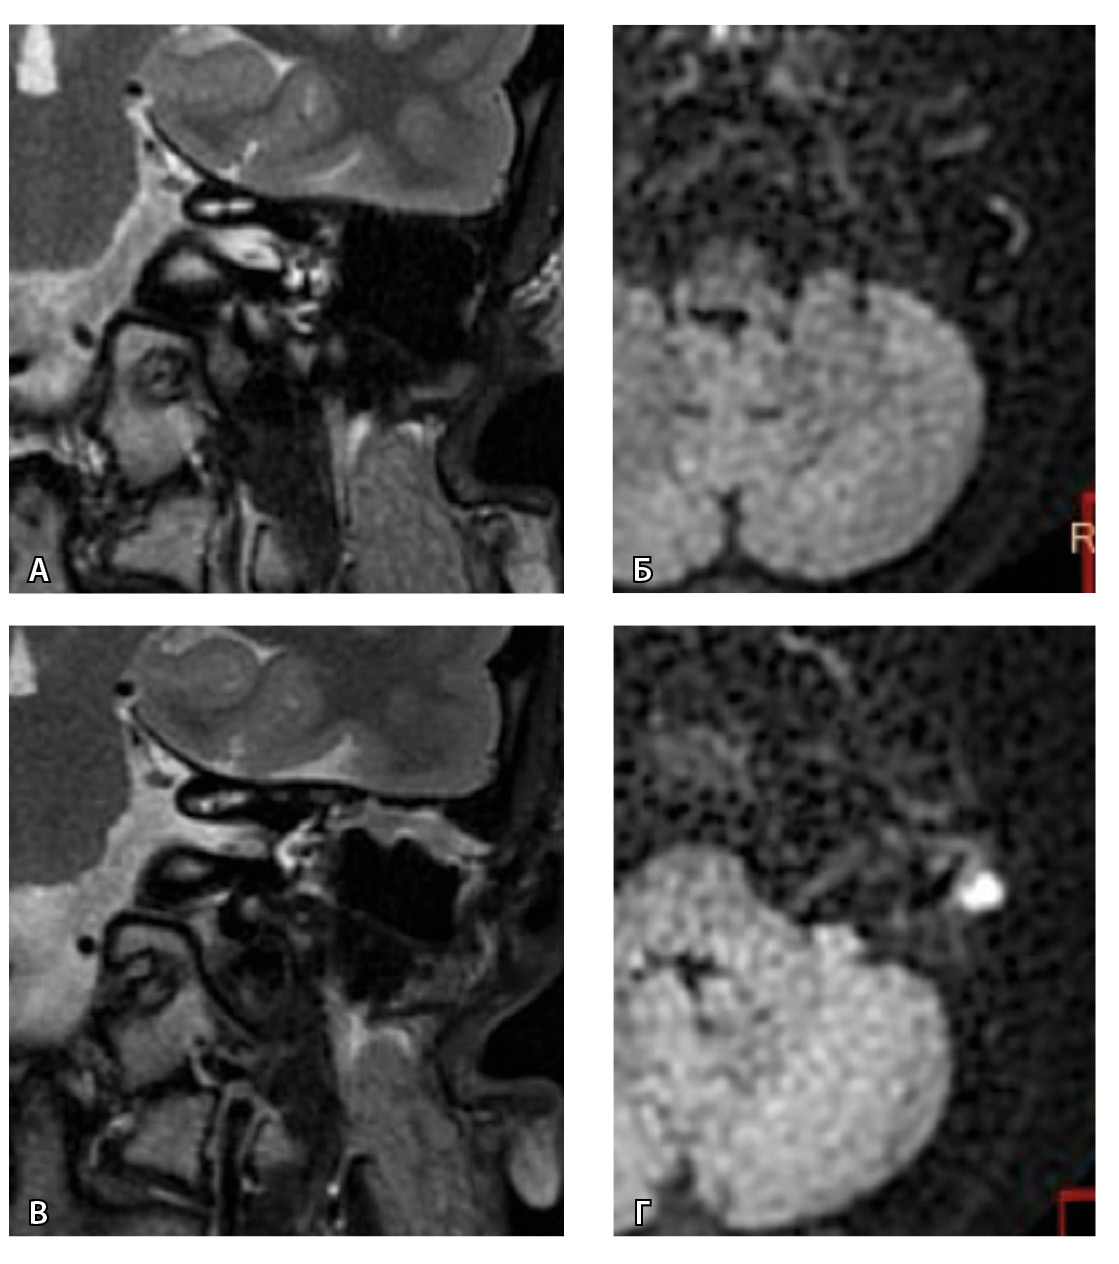

Рис. 3. Хронический правосторонний средний отит. По данным компьютерной томографии (А, Б) нет ремоделирования барабанной полости, деструкции и смещения косточек, скутум сохранен, данных за холестеатому нет. При магнитно-резонансной томографии (В, Г) у того же пациента выявлен очаг высокого магнитно-резонансного сигнала, который при слиянии локализовался в области пространства Пруссака. Заключение и интраоперационно – холестеатома пространства Пруссака